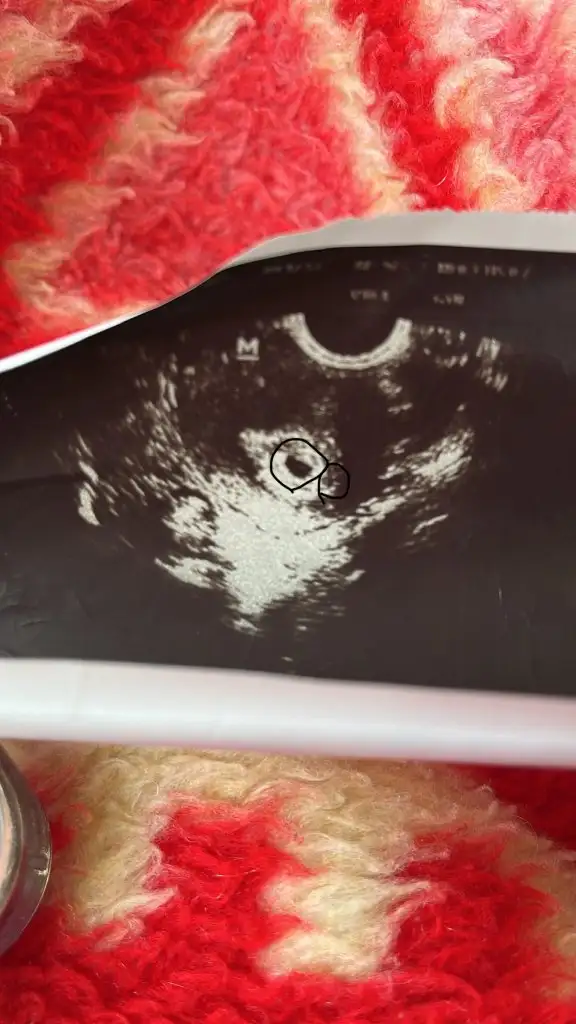

Hayırlı olsun canım sağlıkla kucağına al inşallahEvet alttan muayene ile gözüktü ama ulturasondan çok anlamıyorum

Onu karından ultrasyon ile daha net görebilirsin canım ben 5. Haftada gittiğimde karın ultrasyonu ile görüldü daha net oluyor öyleTeşekkür ederim hepimiz için inşallah tek kese mi var yoksa iki kese mi acaba o küçük olan yansıma mı anlamadım